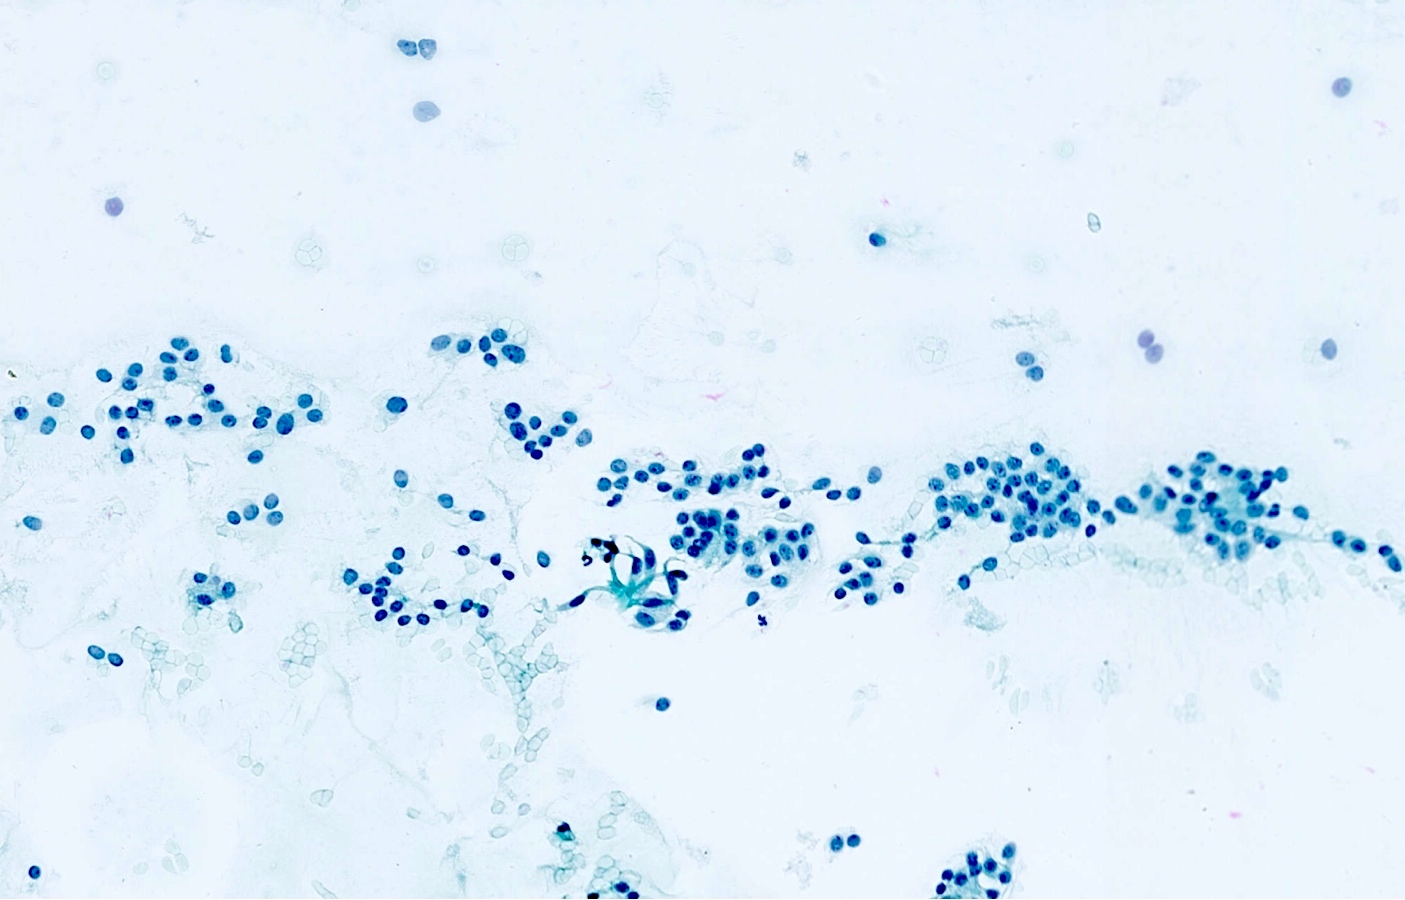

Cytology description

- Loosely cohesive groups and isolated cells sometimes around branching capillaries; rosette structures may be seen (Cibas: Cytology - Diagnostic Principles and Clinical Correlates, 4th Edition, 2014)

- Uniform population of small tumor cells with round / elongated or plasmacytoid shape

- Smooth nuclear outlines, uniform with salt and pepper chromatin and a small nucleolus; no or rare mitoses

- Scant granular cytoplasm

- Absence of molding, nuclear crush and necrosis

Cytology images